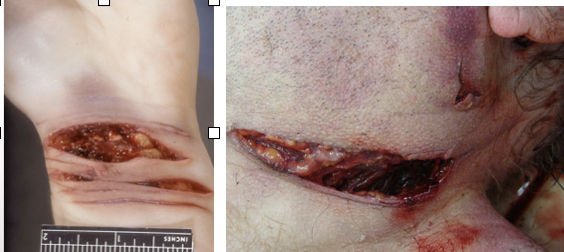

incised wound

clean, cut edges, well-defined, free from contusions

spindle-shaped

lots of hemorrhage from clean cut vessels

deeper at the beginning and more shallow at the end (“tailing”)

defensive wound

grasping surfaces of hands - flap wound created

ulnar border of forearm

dorsum or plantar surface of hand

lower limbs - sexual assault

stab wound

depth > length

width of wound < width of weapon - stretching of skin

clean cut edges

punctures around concealed parts of the body (axilla, vagina, rectum, nostrils)